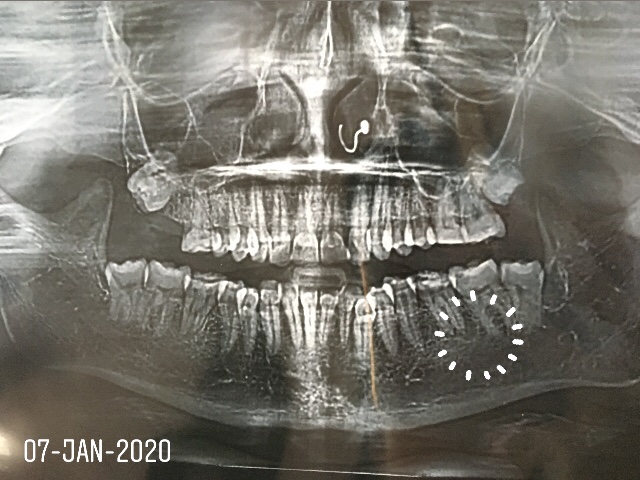

Radiographically,

1. Granulomas form small welldefined radiolucencies.

2. A radicular cyst forms a large well-defined radiolucency with or without a radiopaque (hyperostotic) border.

3. Apical abscess form large radiolucencies with diffuse irregular borders.